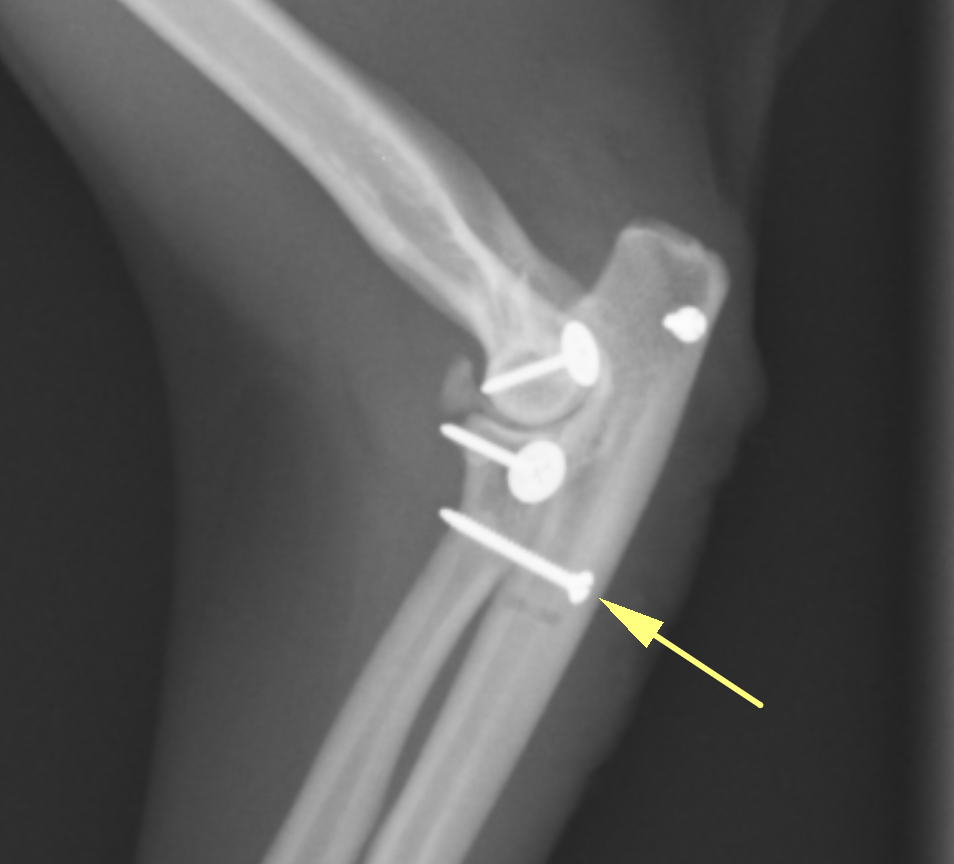

手術ではまず輪状靭帯の再建を行いますが、靭帯を縫合してもすぐに断裂してしまうことから、尺骨から橈骨に向けて一本のスクリューを打ちます。この方法で尺骨と橈骨を固定します。固定すると、腕を捻る方向は動かなくなるため、猫の場合、猫座りやよじ登るときにねじるような動きはやりにくくなります。

この黄色の矢印のスクリューが尺骨と橈骨を固定しています。